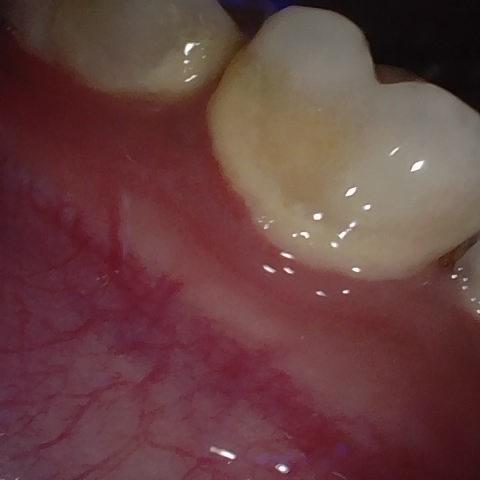

Annotated as "Good"